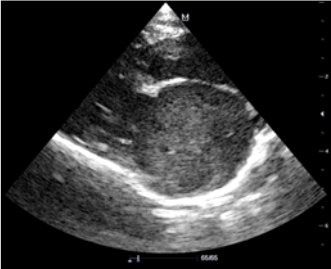

Эхокардиография (рис. 3–5). Данный метод позволяет выявить основное заболевание сердца. Также можно выявить изменение кровотока и замедленное прохождение крови в ушке или в полости левого предсердия посредством импульсно-волнового доплера. У некоторых кошек тромб, формирующийся (в виде облака) или зрелый, можно увидеть в левом предсердии.